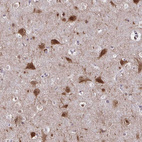

Immunohistochemistry analysis in human cerebral cortex and pancreas tissues using HPA053891 antibody. Corresponding AKAP5 RNA-seq data are presented for the same tissues.